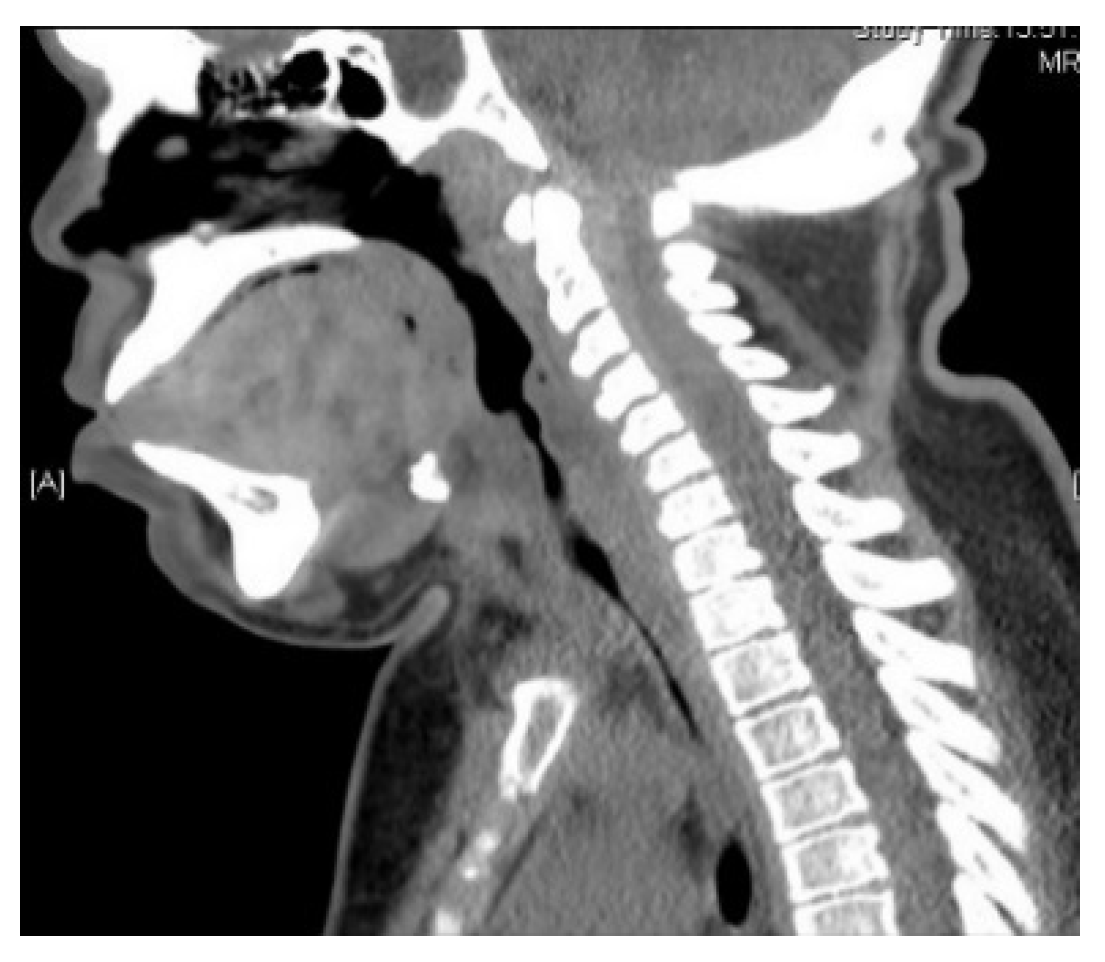

3.2. Cross-Sectional Imaging

3.3. 3-Dimensional Reconstruction (3D) and Virtual Endoscopy (VE)